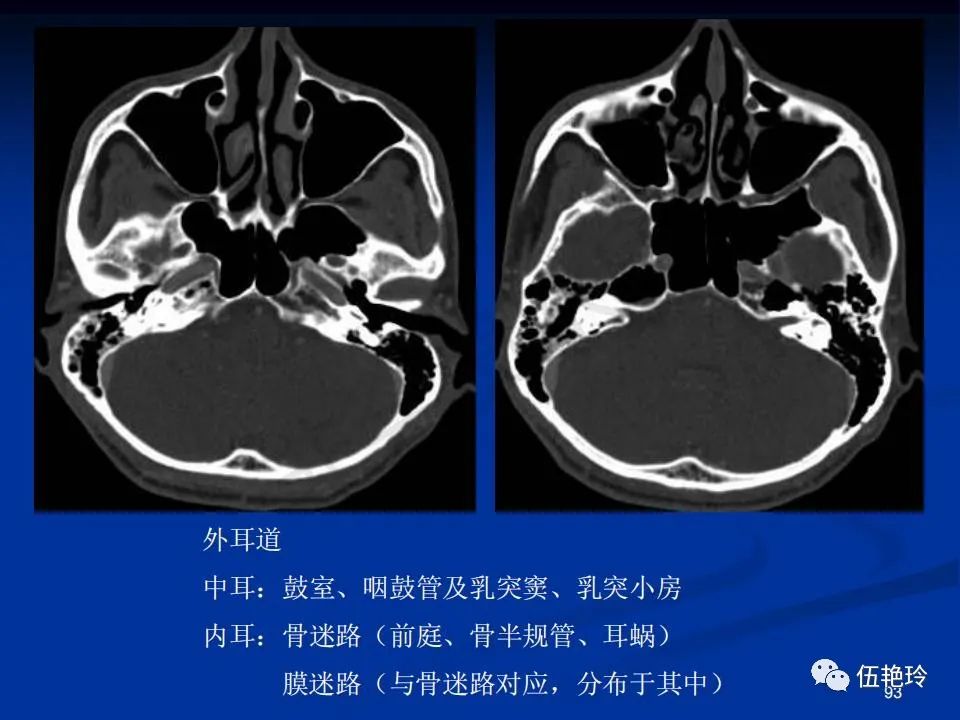

耳与面神经的解剖